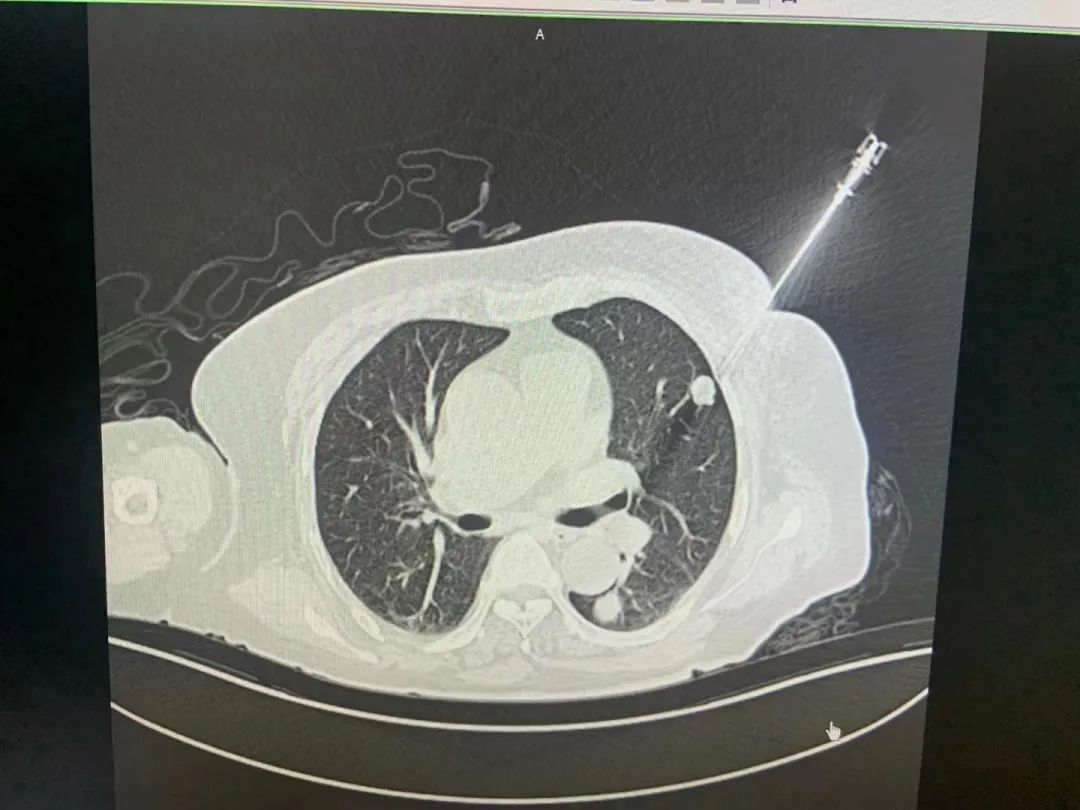

腫瘤穿刺機(jī)器人是睿觸科技成立后生產(chǎn)的第一款產(chǎn)品,如今已經(jīng)在長(zhǎng)三角兩家??迫揍t(yī)院開(kāi)展臨床試驗(yàn)。這款手術(shù)機(jī)器人不僅將穿刺活檢精度提高了十倍以上,而且將穿刺時(shí)間縮短了數(shù)十倍,極大提高了手術(shù)效率和便捷度,降低了病人的痛苦。

“人體的腫瘤藏在很深的組織里,必須通過(guò)醫(yī)學(xué)影像,也就是CT等技術(shù)來(lái)查找。”劉劍解釋道,按照傳統(tǒng)的操作方法,腫瘤穿刺中手術(shù)機(jī)器人必須借助醫(yī)學(xué)影像來(lái)進(jìn)行引導(dǎo),然而這兩者之間其實(shí)是“互相不認(rèn)識(shí)的”關(guān)系?!耙?yàn)镃T和機(jī)器人是各自獨(dú)立的兩套坐標(biāo)系,必須借助光學(xué)傳感器來(lái)建立聯(lián)系,但這樣也會(huì)導(dǎo)致精度的損失,成像效果不理想,影響手術(shù)進(jìn)程?!币虼耍S|科技將這兩者進(jìn)行了大膽結(jié)合,用劉劍的話說(shuō),就是“讓他們互相認(rèn)識(shí)對(duì)方”。

“我們采取了全新的設(shè)計(jì),把人體的三維腫瘤信息實(shí)時(shí)地告訴機(jī)器人,讓機(jī)器人開(kāi)啟智慧之眼,比如距離有多遠(yuǎn)、角度差了多少度等等,這樣就能引導(dǎo)醫(yī)生來(lái)做更精準(zhǔn)的腫瘤治療手術(shù)?!比绱耍谀[瘤早篩領(lǐng)域,這樣一款精確、快速、安全的經(jīng)皮穿刺手術(shù)機(jī)器人,能讓更多腫瘤患者可以早發(fā)現(xiàn)、早診斷、早治療。